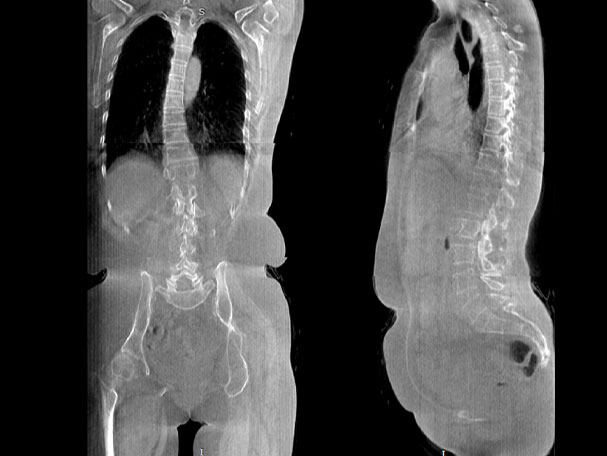

· 补位CT,提供负重位三维影像

· 引领普放走向三维精准诊断时代

填补常规CT/MR空白

助力术前规划和术后评估

VR体绘制重建